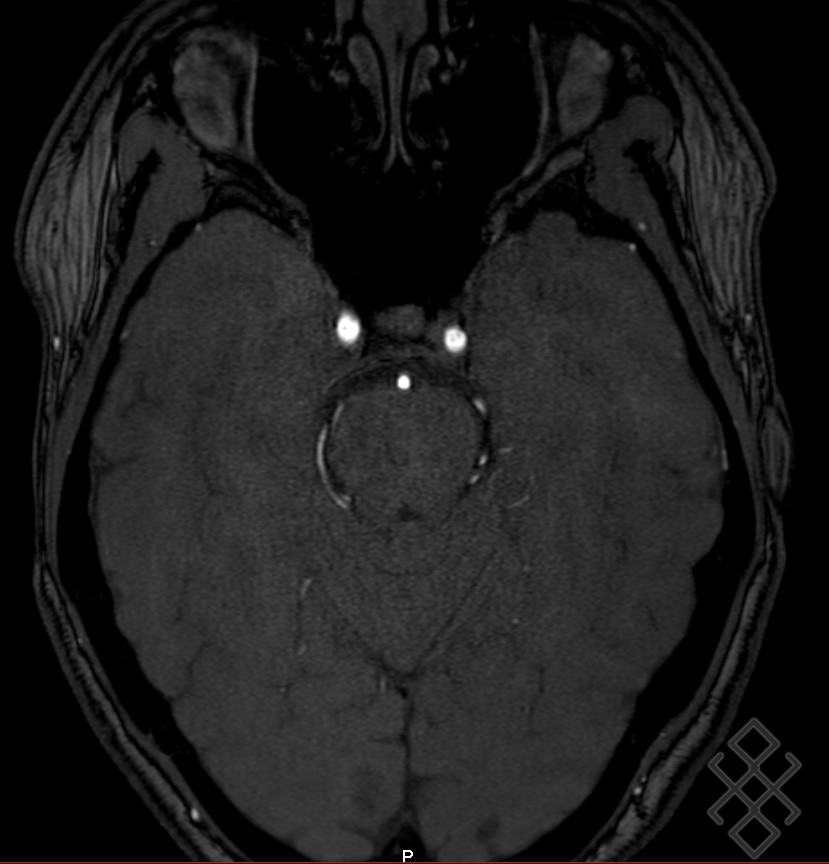

Imagerie par résonance magnétique (IRM) cérébrale en séquence T2 Download Scientific Diagram. Cet examen est nécessaire pour étudier certains troubles de la vision ou de l'oculomotricité. L'IRM de la tête isole des structures encéphaliques invisibles jusqu'à présent, dans différents plans, sur les voies optiques horizontales « de la cornée à la scissure calcarine » (Plans Neuro-oculaire (PNO), Neuro-Oculaire Trans-hémisphérique Oblique (PNOTO) et Neuro-OculoBandelettique (PNOB)), dans leur organisation orthogonale.

La tractographie et l'IRM fonctionnelle ne sont pas utilisées en routine, mais au cas par cas Cependant, il est fréquent de demander une imagerie IRM injectée, principalement pour rechercher un diagnostic différentiel (neuropathie optique rétrobulbaire (NORB), tumeur orbitaire, Drüse papillaire, atteinte des voies visuelles postérieures) ou des signes de leucopathie microvasculaire cérébrale dans les formes non artéritiques. La RMS s'adresse aux médecins de premier recours, mais aussi aux spécialistes des diverses disciplines médicales, aux médecins assistants et chefs de clinique, aux étudiants et aux autres professionnels de la.